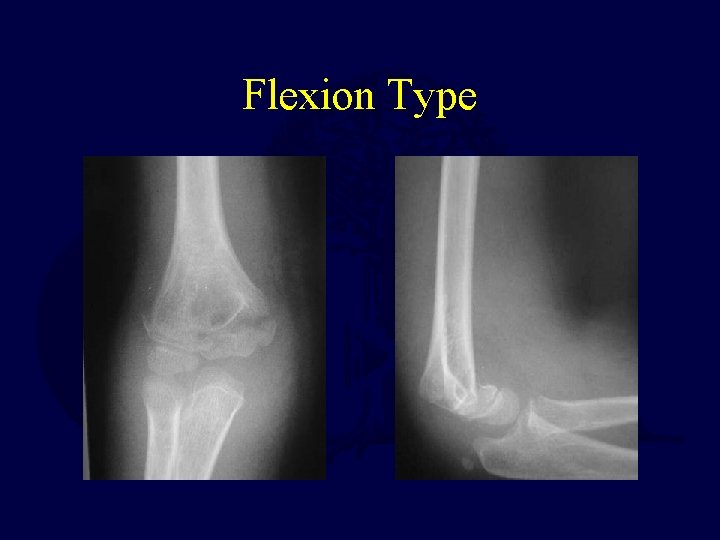

Supracondylar Humerus Fractures Flexion type • Rare, only 2% • Distal fracture fragment anterior and flexed • Ulnar nerve injury more common • Reduce with extension • Often requires 2 sets of hands in OF – Hold elbow at 90 degrees after reduction to facilitate pinning Mahan. Operative management of displaced flexion supracondylar humerus fractures in children. J Pediatr Orthop. 2007; 27: 551.

Flexion Type